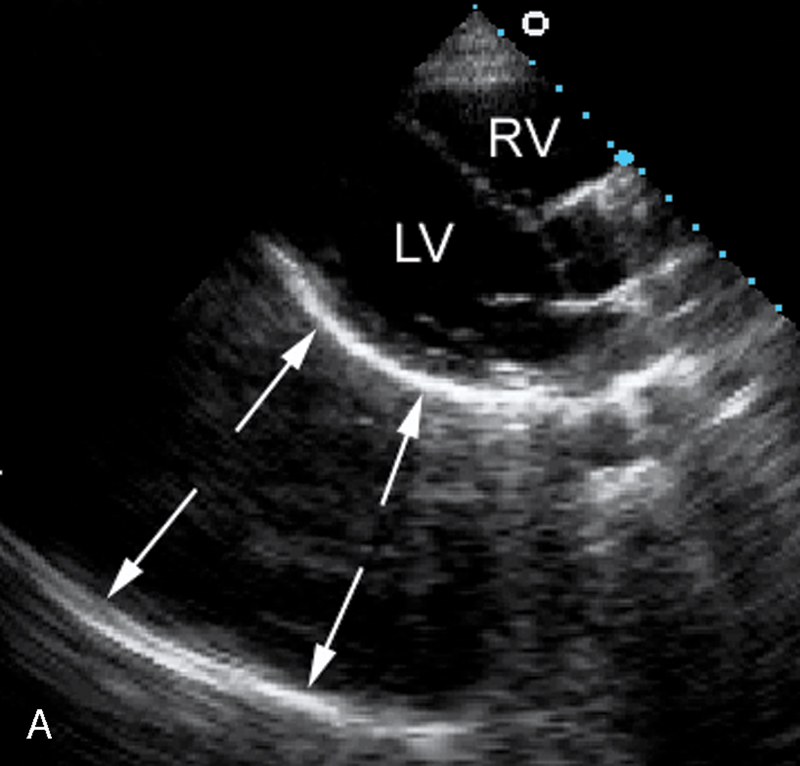

فحوصات تشخيصية لبعض امراض القلب والشرايين التاجية